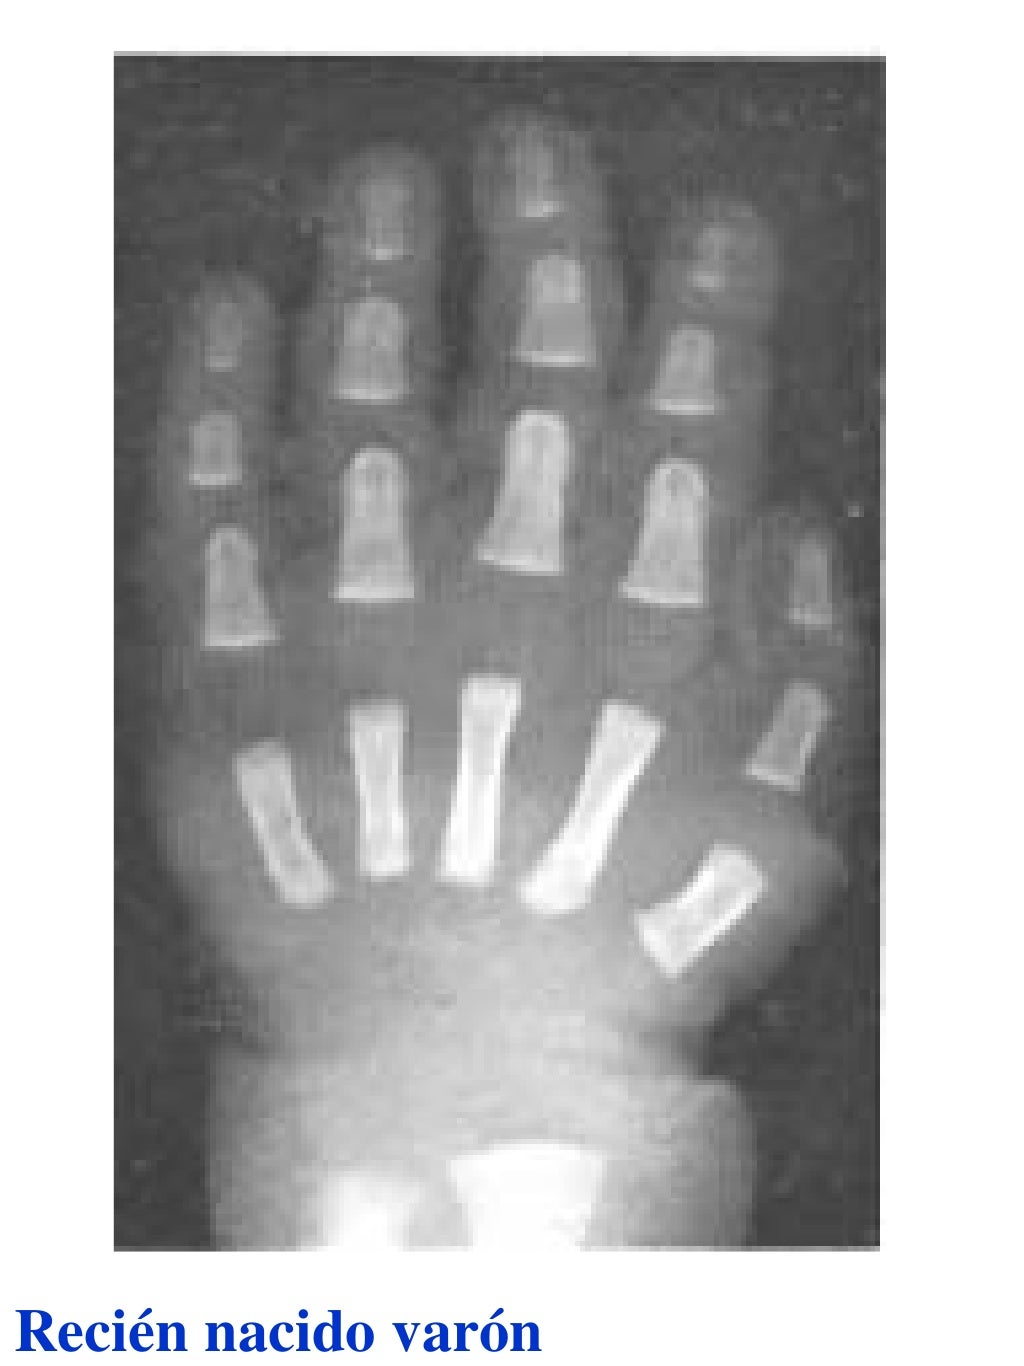

Tablas De Greulich Y Pyle . Scribd is the world's largest social reading and publishing site. This systematic review summarizes the. The radiographic atlas of skeletal development of the hand and wrist by ww greulich and si pyle is a classic radiological. The standards established by greulich and pyle, undoubtedly the most popular method, consist of two series of standard plates. The greulich and pyle method is one of the two main ways to assess the bone age of children. El documento lista las edades. Both main methods of bone age. 153 recomendaciones • 616,869 vistas. Atlas greulich y pyle | pdf | descarga gratuita. The greulich and pyle atlas is used to estimate the age of children and adolescents.

Tablas De Greulich Y Pyle The standards established by greulich and pyle, undoubtedly the most popular method, consist of two series of standard plates. The standards established by greulich and pyle, undoubtedly the most popular method, consist of two series of standard plates. El documento lista las edades. This systematic review summarizes the. The greulich and pyle method is one of the two main ways to assess the bone age of children. Both main methods of bone age. Scribd is the world's largest social reading and publishing site. 153 recomendaciones • 616,869 vistas. Atlas greulich y pyle | pdf | descarga gratuita. The greulich and pyle atlas is used to estimate the age of children and adolescents. The radiographic atlas of skeletal development of the hand and wrist by ww greulich and si pyle is a classic radiological.